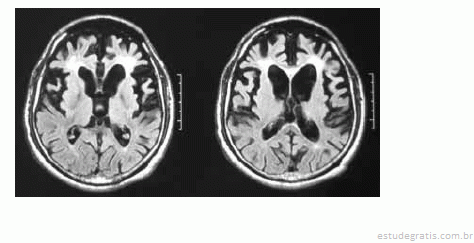

Uma mulher de 55 anos de idade, sem comorbidades, há três anos começou a apresentar distúrbio do comportamento, comprometimento do senso moral, da autocrítica, do poder de abstração e da memória. No exame, ela pouco colaborava com o examinador, possuía uma rigidez axial e apendicular, além de sutil tremor em repouso. O exame de imagem (RNM) a seguir foi realizado para auxiliar o diagnóstico.

Com base nesse quadro clínico, julgue os itens subsequentes.